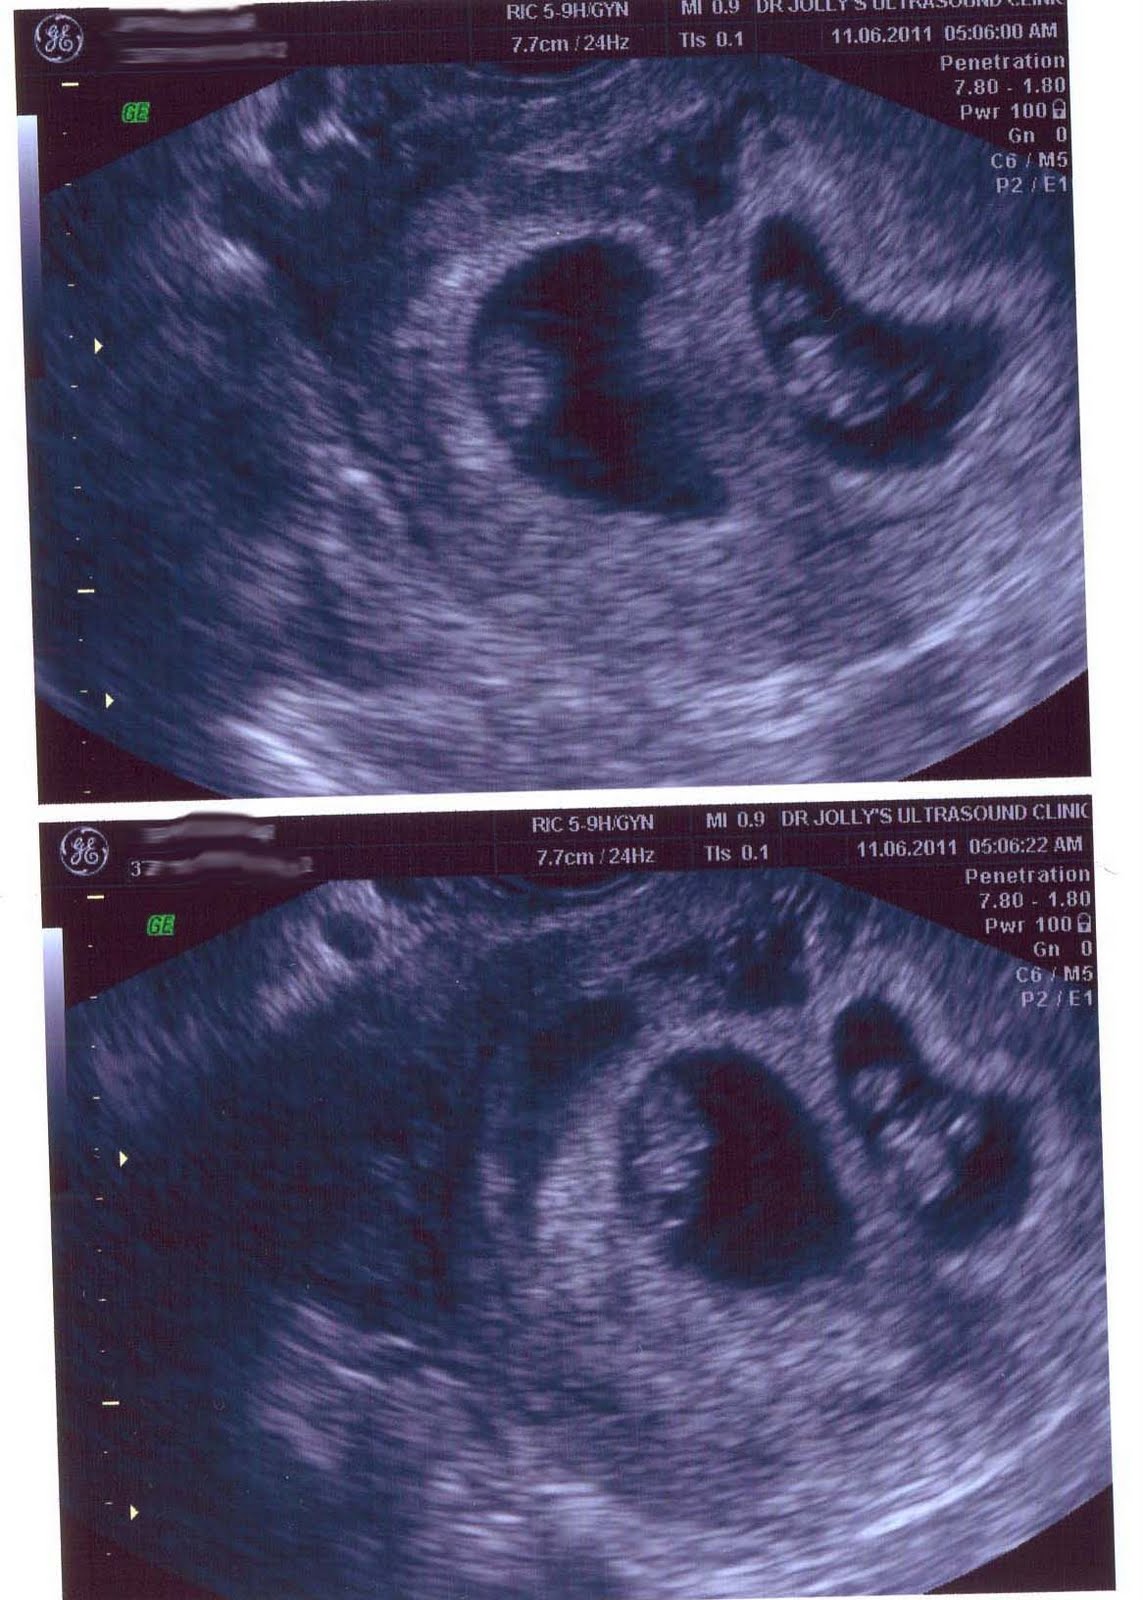

He recibido una nueva ecografía, sorprende ver como crecen los embriones, que ilusión, y que ganas de que el tiempo pase y todo salga bien.